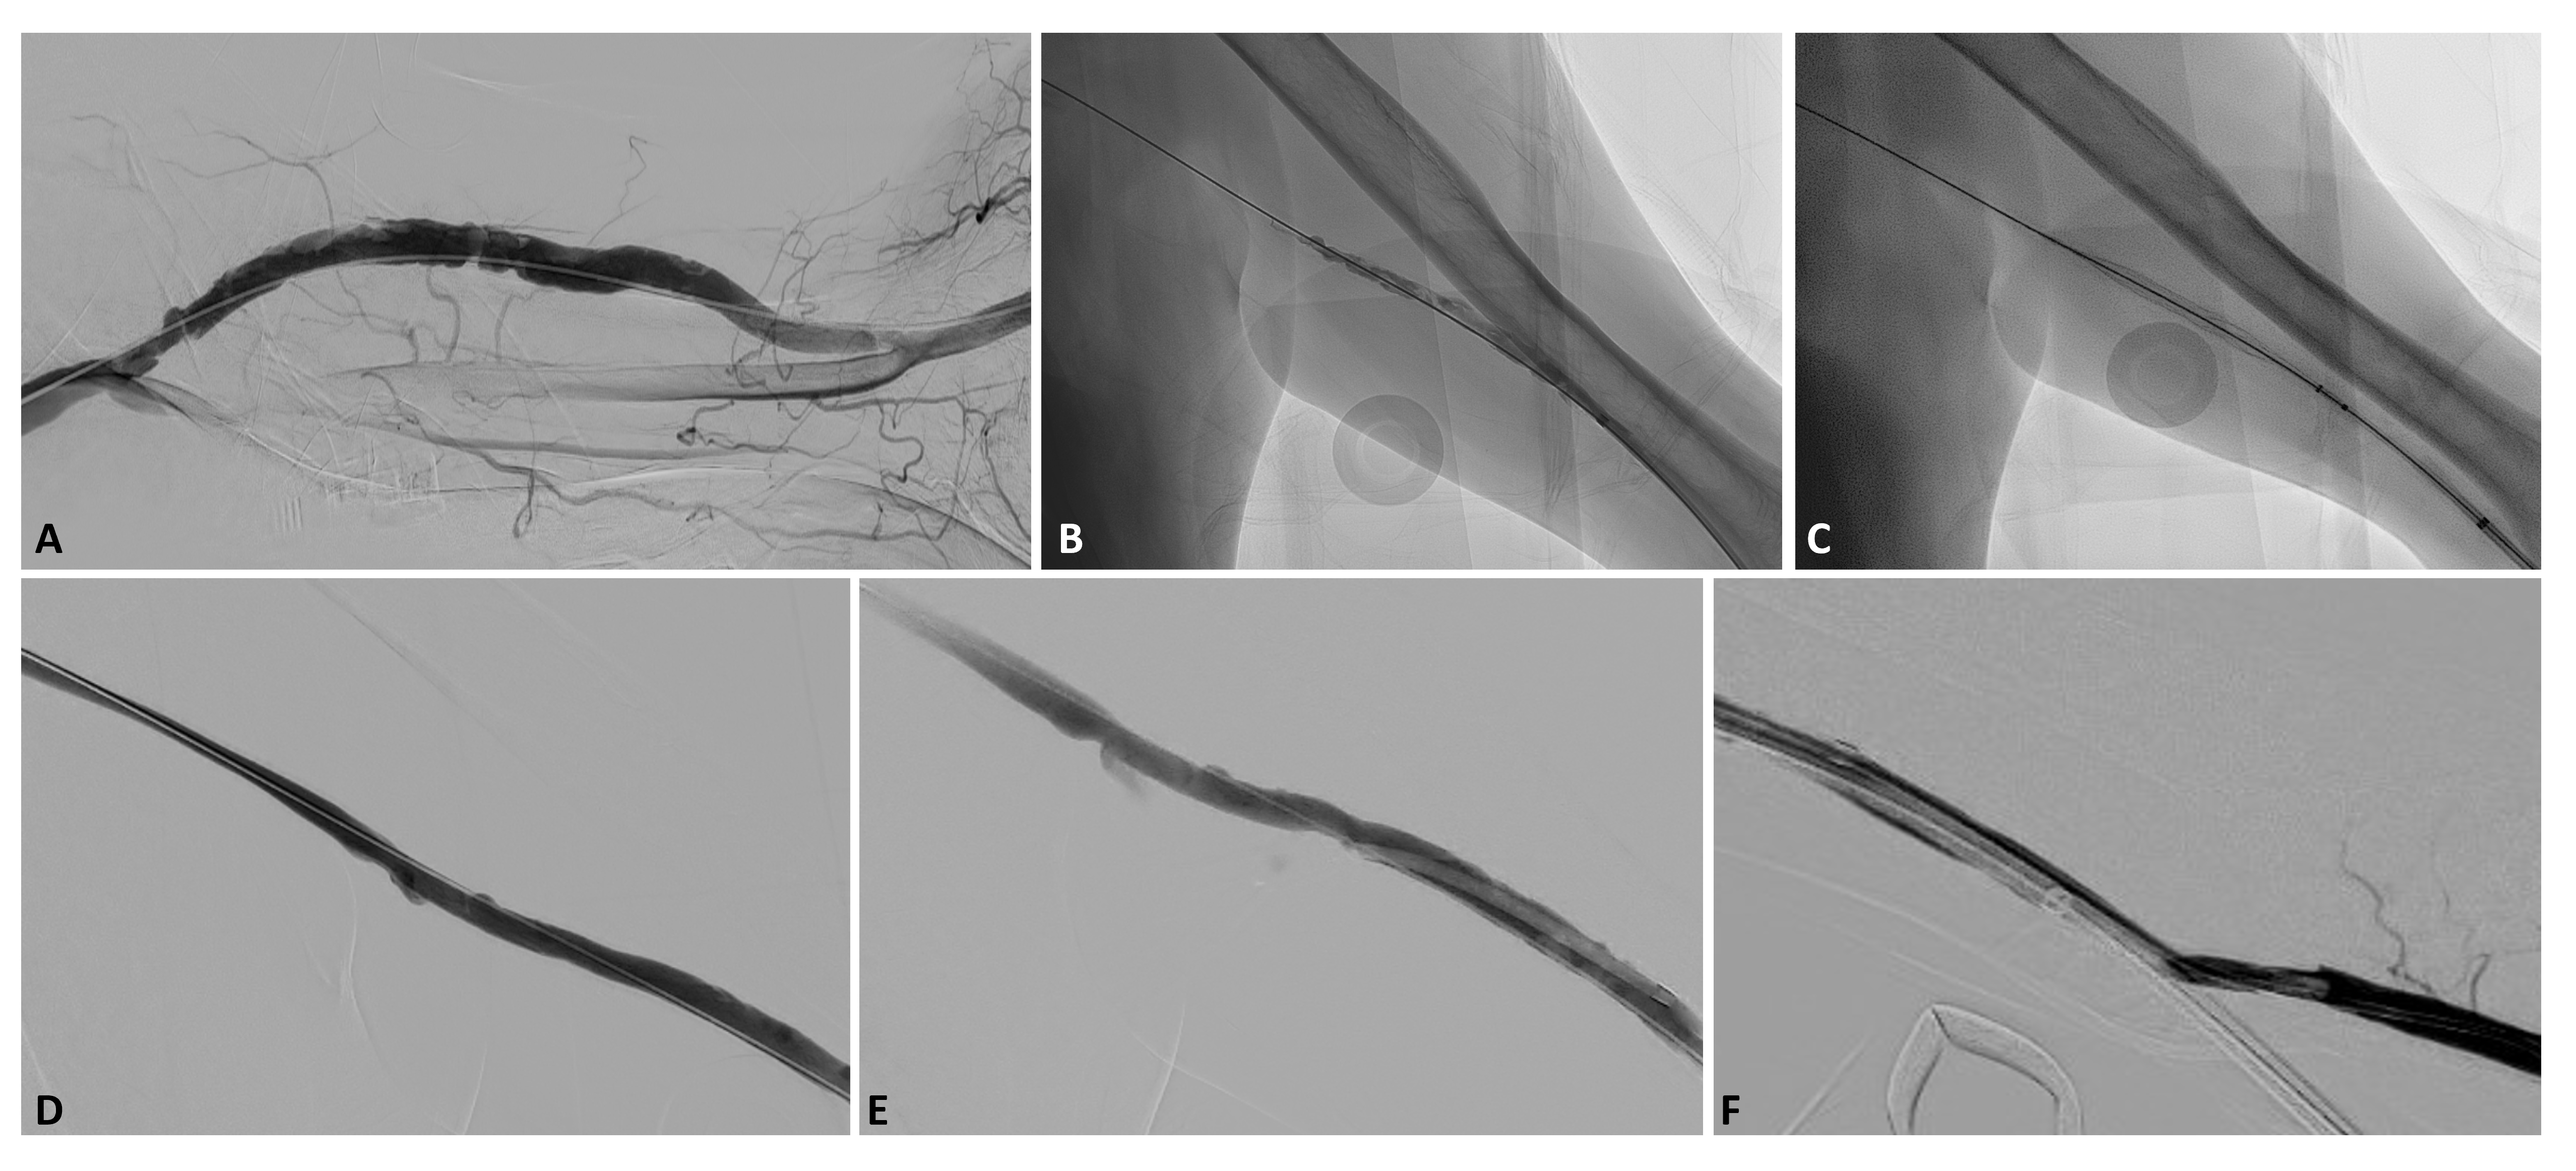

Case 2. A 52-year-old male with history of cirrhosis, hypertension, type 2 diabetes, and ESRD on hemodialysis via a left upper extremity arteriovenous graft presented with a clotted access. A left upper arm brachial artery to axillary vein graft was surgically placed in July 2022 using a 7mm-4mm tapered Gore-Tex graft.

The patient initially presented in October 2022 with thrombosed access. Declot with angioplasty and rheolytic thrombectomy was performed through a left transradial arterial access via a 6 Fr slender sheath. At procedural completion, the graft was noted to be grossly patent but with residual filling defects within the access (Figure 5A).

Unfortunately, the patient returned to interventional care when the graft clotted less than a month later in November 2022. Using Seldinger technique and sonographic guidance, the graft was accessed with needle and wire pointed towards the venous outflow. After upsizing to a short 6 Fr vascular sheath, a Kumpe catheter and angled Glidewire were used to navigate into the central veins. Pullback venogram revealed thrombosis only of the access itself which was full of irregular filling defects (Figure 5B).

Subsequently, after obtaining access to the IVC, an .035-inch Advantage Glidewire was placed into the IVC. Serial dilatation was performed to 10 Fr and subsequently 12 Fr. Then, an InThrill sheath was placed into the access and the funnel was deployed.

The patient was systemically heparinized. Thereafter, multiple rounds of thrombectomy were performed of the access using the Inthrill thrombectomy catheter (Figure 5C). These maneuvers yielded small amounts of subacute and chronic appearing thrombus. Repeat angiogram was performed revealing a stenosis at the venous anastomosis, which was treated with balloon angioplasty up to 7 mm.

Only after establishing patency of the access, a retrograde access was obtained using Seldinger technique. A Kumpe catheter and .035-inch angled Glidewire were used to cross into the brachial artery. Then, the Fogarty maneuver was repeated three times over an .035-inch wire.

Immediately upon pulling the plug, a palpable thrill was felt in the fistula. An angiogram was again performed, demonstrating a patent arterial anastomosis, patent access, and patent venous anastomosis as well as central veins (Figure 5D-F).

After closure using an over-the-wire suture technique, the graft was examined. There was an excellent thrill with no pulsatility.

The patient was returned to dialysis three times a week without issues. During clinic follow-up at 12 weeks, the patient reported that his graft has a more robust and readily palpable thrill now than it ever has, including after initial surgical placement or after the initial declot procedure. His graft remains open at now over 12 weeks follow-up.